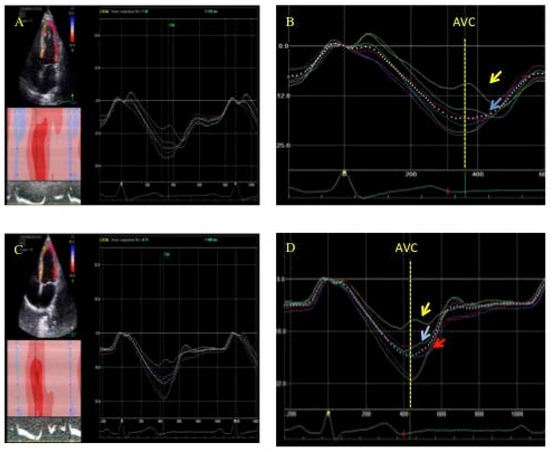

3.1. Postsystolic Shortening